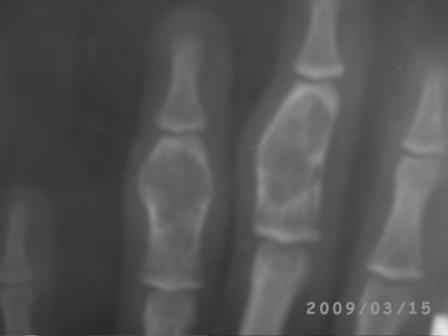

Re: Непонятный процесс в основной фаланге пальца

Уважаемый Юрий, действительно, онкологи делали пункционную биопсию.

Конечно, мы во время операции будем брать материал на гистологию, а также удаление очага и замещение аутотрансплантатом тоже в плане рассматривается, как на примере, которая была представлена на форуме. правда снимки не очень качественные, прощу извинения!

Коллеги, почти уверен, что эти два случая поражения фаланг имеют различный генез. Простое выявление хрящевой ткани в биопсийном материале, увы, не дает еще диагноза.. Хотя местное лечение (если оно необходимо) может быть сходным. Единственное, не стал бы увлекаться широкими резекциями и массивными костными пластиками в детей.